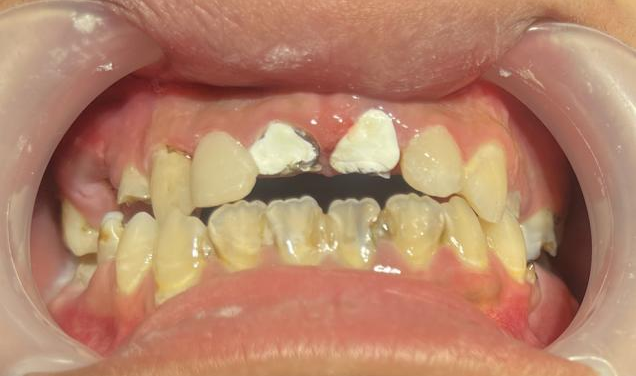

近日,广州市花都区人民医院口腔科通过规范的诊疗流程,为一名18岁男孩完成牙齿“蜕变”,让其重拾自信笑容。

这名男孩就诊时满口黑牙,颜值大打折扣。广州市花都区人民医院口腔科结合放射检查、内科治疗、外科干预及修复重建等诊疗环节,制定了“拍片检查—牙周治疗—拔牙—根管治疗—桩冠修复”的系统性方案,后续还将为其缺失牙进行种植修复。